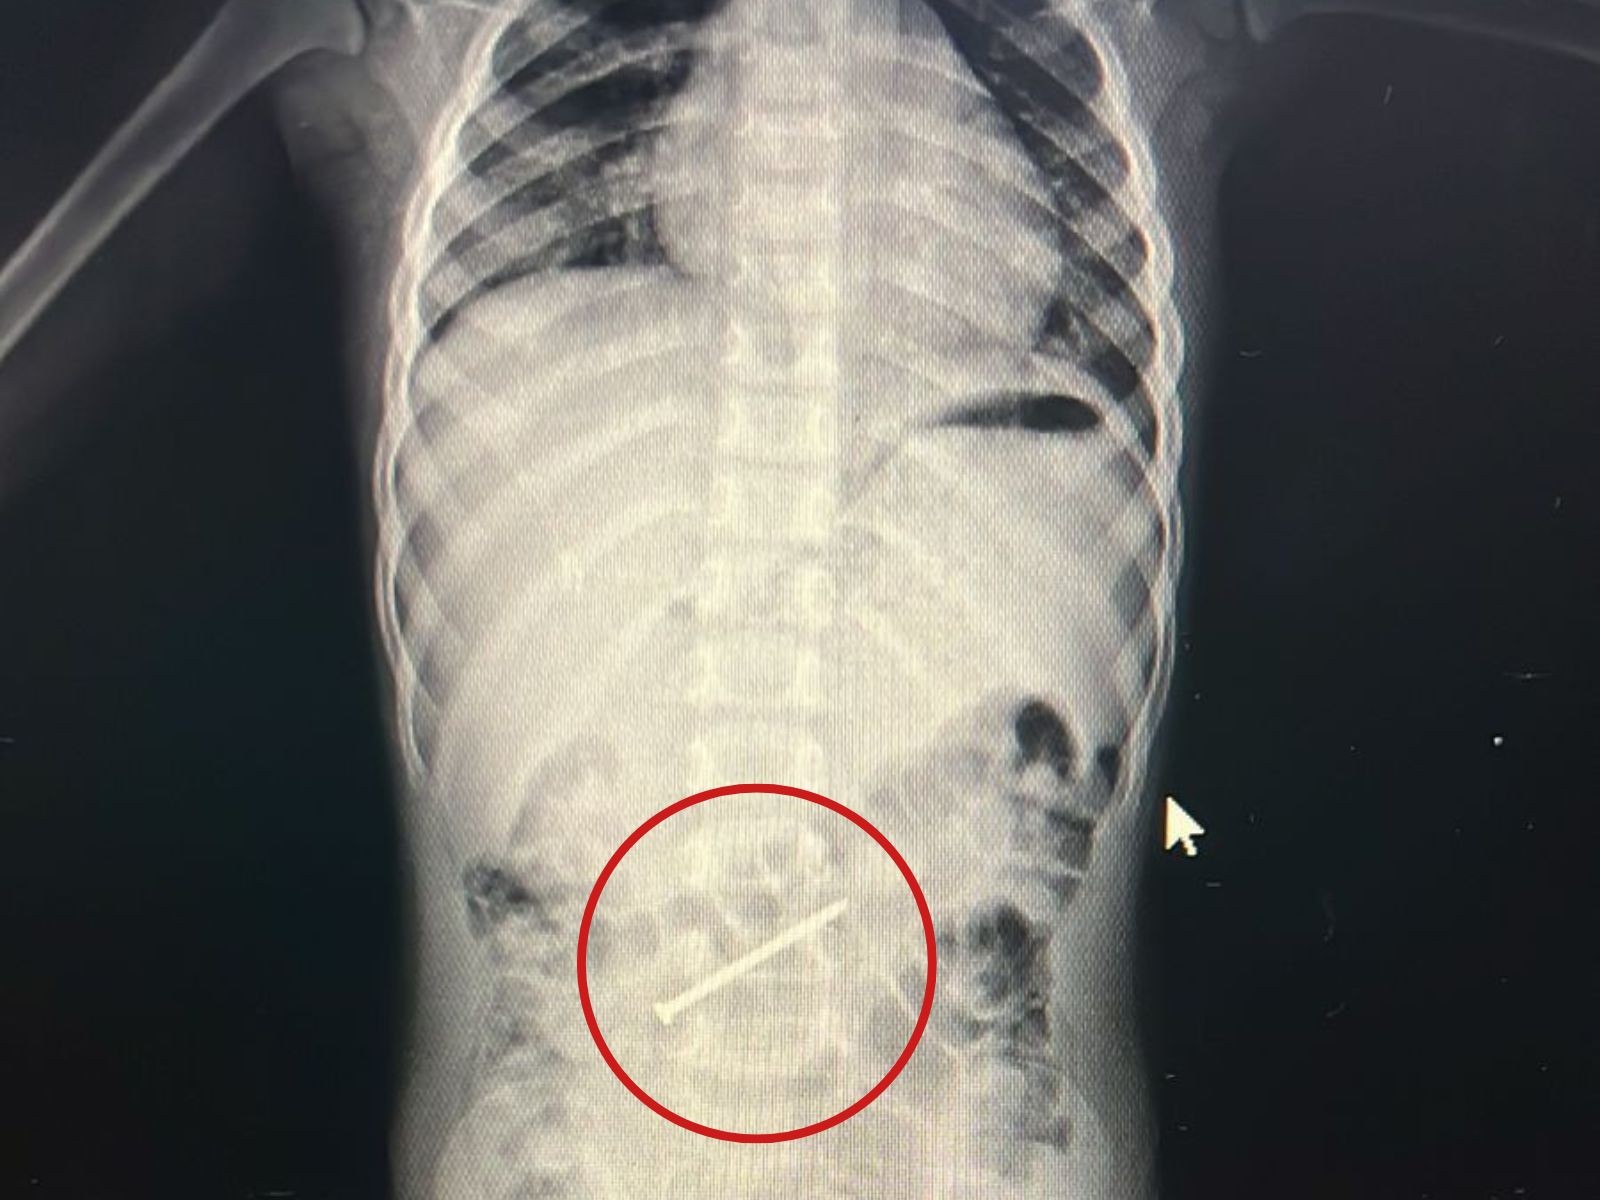

Menino de 3 anos passa por colonoscopia para retirada de prego no intestino no AC

16/01/2026 - Prego estava no intestino grosso da criança

Um menino de 3 anos passou por uma colonoscopia na tarde desta sexta-feira (16) no Hospital Regional do Juruá, em Cruzeiro do Sul, interior do Acre, para retirada de um prego do intestino grosso. A criança está internada desde a última quarta (14) e passa bem.

O menino é de Ipixuna, cidade do Amazonas, e foi levado para Cruzeiro do Sul, junto com a mãe, para ter um atendimento especializado. O prego tinha seis centímetros.

"É um objeto pontiaguado, havia o risco de perfurar o intestino. Como não estava descendo, ficou parado dois dias no mesmo lugar, optamos pela colonoscopia. Foi um procedimento tranquilo", destacou.